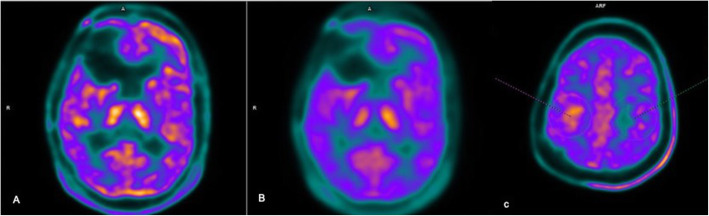

C11 methionine PET images were loaded into SIEMENS SYNGO Via (VB30) workstation after correcting for partial volume effects (PVE) using Siemens E7 tools (Fig. 1A, B). The 3D ROI was drawn semi-automatically using an individually adapted isocontour of the tumor maximum using a standard ROI with a fixed diameter of 1.6 cm centered on the tumor maximum yielding a volume of 2 ml (Fig. 1C). Similar mirror ROI was placed in the contralateral brain parenchyma to calculate the background /normal brain parenchymal uptake (Fig. 1C). The values SUVmax and SUVmean were obtained for both tumor and normal brain parenchyma and tabulated. Ratio TBR max and TBR mean (tumor to normal brain/background) were calculated for statistical analysis.

Fig. 1.

LIST mode UTE MRAC sequence reconstructed PET images (A) and images reprocessed on E7 tools SIEMENS for correction of partial volume effects (PVE) (B). 3D ROI was drawn semi-automatically using an individually adapted isocontour of the tumor maximum using a standard ROI with a fixed diameter of 1.6 cm centered on the tumor maximum yielding a volume of 2 ml (C)